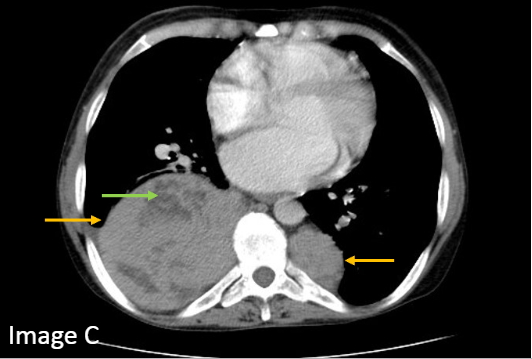

The frontal chest radiograph shows a lobulated soft tissue masses (image A, red arrow), much greater on the right. The lateral radiograph localizes the mass to the posterior mediastinum (image B, yellow arrows).

正位胸部X线片显示分叶状软组织肿块(图A,红色箭头),右侧较大。 侧位X线片显示肿块位于后纵隔(图B,黄色箭头)。